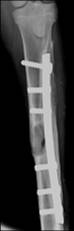

長春應化所科技人員在國家“863計劃”課題的支持下,通過與在生物可吸收導電高分子,羥基磷灰石納米復合材料和電刺激定向誘導組織再生等方面進行了研究,國際上首先將生物可吸收的導電高分子共聚物與電刺激技術相結合應用于骨科修復,開發了電活性智能骨修復材料、骨科固定融合器件和電刺激增強骨再生等新技術,在提高材料的生物降解性、力學性能、成骨生物活性和有效持續控制生長因子基因釋放等方面取得進展。所制備的材料和器件具有良好的生物相容性,達到了國家對植入材料的生物安全性要求。材料的細胞擔載能力明顯提高,具有骨傳導和誘導活性,對骨缺損的愈合能力和愈合質量有明顯提高。課題實施期間申報國家發明專利 14 項,發表 11 篇學術論文,其中5 篇發表在Biomaterials, Biomacromolecules等生物材料領域的國際著名刊物上。該課題完成了相關的動物實驗,顯示了良好的臨床應用前景。

0 3 12W 24W 44W